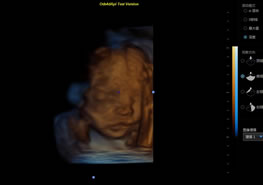

> 3D/4D成像技術/限7800選配